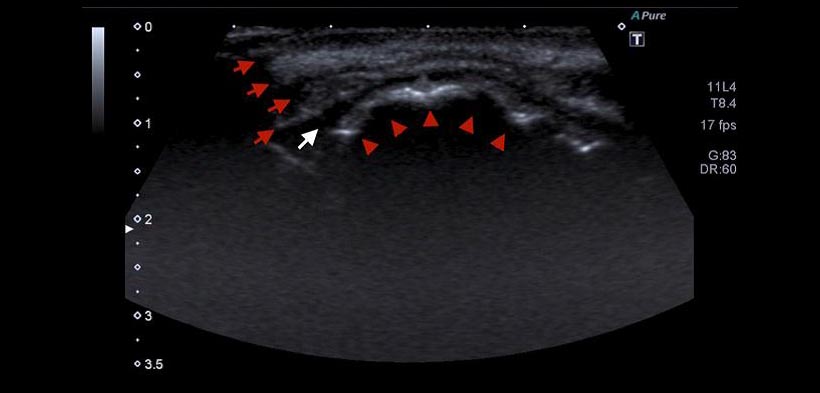

En las imágenes de la USG, las estructuras anatómicas normales se pueden evaluar al inicio del tratamiento (fig. 2), antes de la expansión, y luego durante el tratamiento, definiendo de esta manera etapas en el proceso de expansión de la sutura palatal.

En las etapas de la ERP (T0, T1 y T2), el área de expansión se caracteriza por una imagen hiperecoica (similar a imágenes radiopacas en las radiografías) no homogéneas, zonas bien delimitadas.

En la USG se observan las estructuras anatómicas normales (fig. 3 y 5). Las superficies del hueso cortical son fácilmente identificadas. Sin embargo, la evaluación de la sutura palatina media es casi imposible, debido a la presencia de hueso cortical intacto y grueso, en la superficie que refleja rayos de ultrasonido, lo que hace imposible que el equipo pueda hacer lectura a ese nivel. La sutura palatina media aparecen en las radiografías oclusales como una línea radiolúcida delgada en la línea media entre las dos partes de la pre-maxilar.

Figura 2. Imágenes de una ecografía del maxilar superior, se muestran las estructuras anatómicas normales en un paciente con pre-expansión de la sutura media palatina. Flechas superiores muestran al músculo orbicular de los labios, la flecha blanca muestra el área del vestíbulo, las flechas inferiores muestran el hueso cortical y las fronteras del maxilar superior.